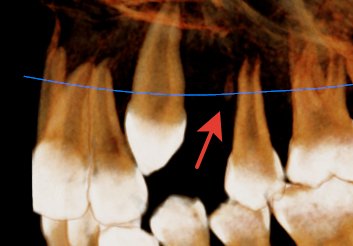

Ребенку 12 лет удалили здоровый зуб, четверку, чтобы дать возможность на освободившееся место выйти тройке (как я понял), при удалении остался кусок корня, размерами 3мм и врач сказал, что ничего делать не нужно, все ок. Очевидно, что в понедельник схожу к другому врачу, обсудить, может все-таки это не нормальная история, оставлять ситуацию вот так. Городок у нас очень маленький, может кто из спецов стоматологов-хирургов наткнется, нужный вектор скорректирует, настаивать мне на его извлечении или это нормальная практика в стоматологии оставить, раз зуб был здоров и риски его инфицирования минимальны, хотя представляется, что со средой полости рта он наверняка провзаимодействовал. Ну и фото с прибора, может я там и не правильно смотрю, но думаю, что не ошибаюсь.